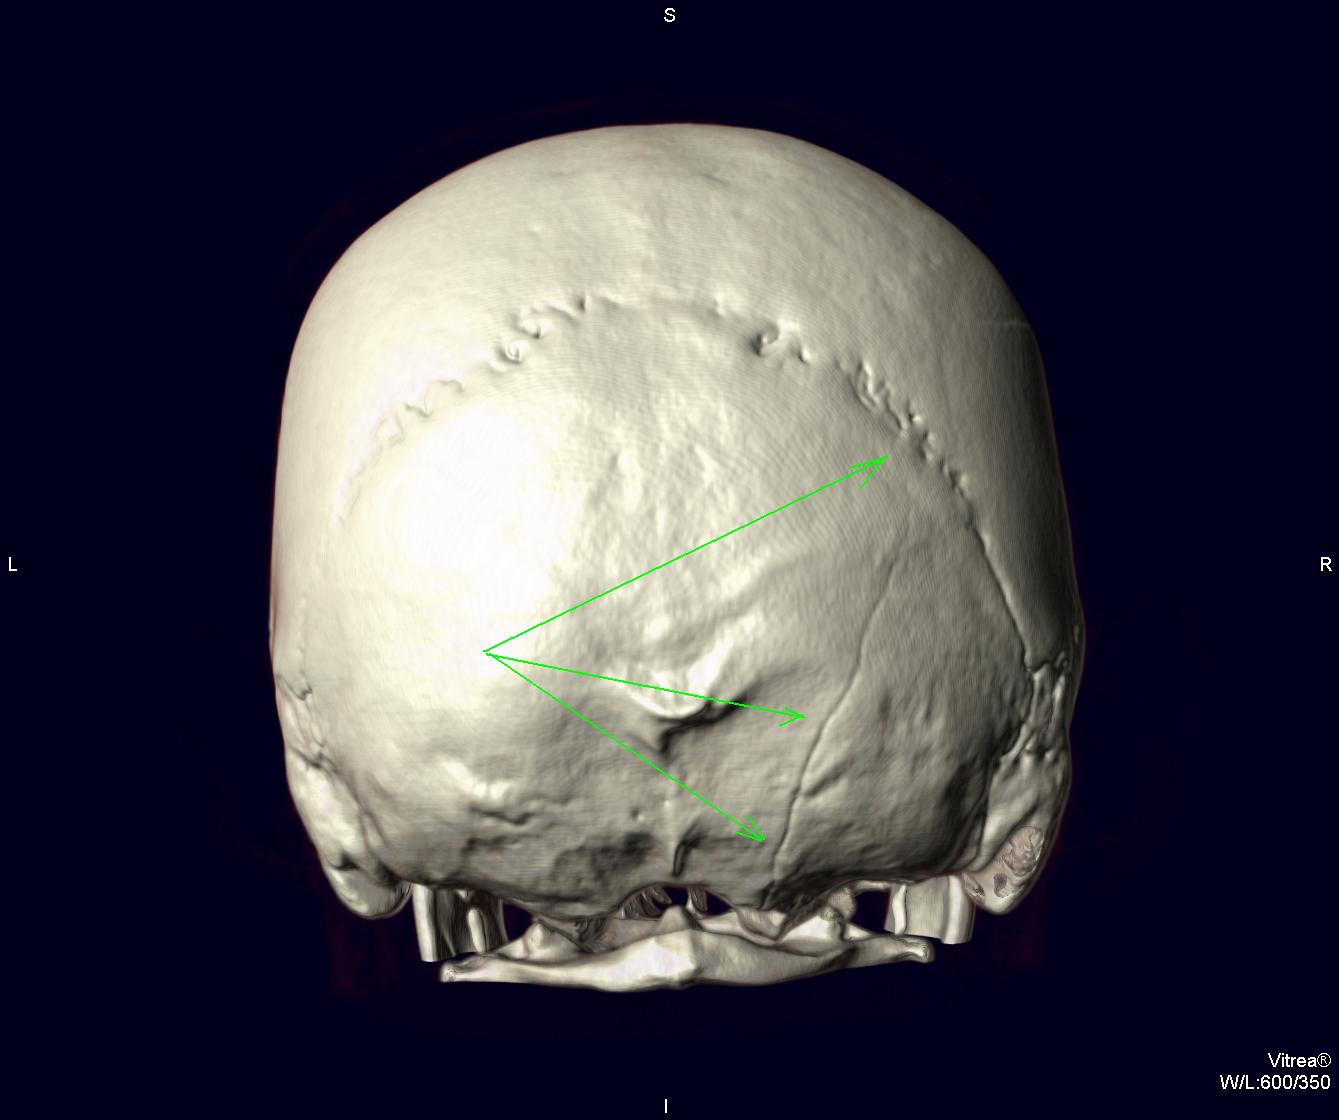

ИзображениеИзображениеИзображениеИзображениеИзображениеИзображениеСвежая травма. Эти изображения демонстрируют возможности МСКТ. Виден линейный перелом затылочной кости справа с переходом на основание черепа. Линейный перелом лобной и теменной костей слева с симптомом молнии (изменение хода перелома при пересечении шва). Симптом молнии один из пяти признаков линейного перелома, описанные по обычным рентгенограммам.

"Виден линейный перелом затылочной кости справа с переходом на основание черепа. Линейный перелом лобной и теменной костей слева с симптомом молнии (изменение хода перелома при пересечении шва)."

На мой взгляд, (взгляд не профессионала в этом виде исследования) линия перелома, помеченная красными стрелками заканчивается на уровне зеленой стрелки.

Мне кажется, что это не один перелом, а два самостоятельных перелома.

Да, здесь два перелома: 1. затылочной кости, 2-ой теменной с переходом на лобную через венечный шов.

P.S. Извините, я часто путаю право-лево. Оба перелома, конечно, справа.